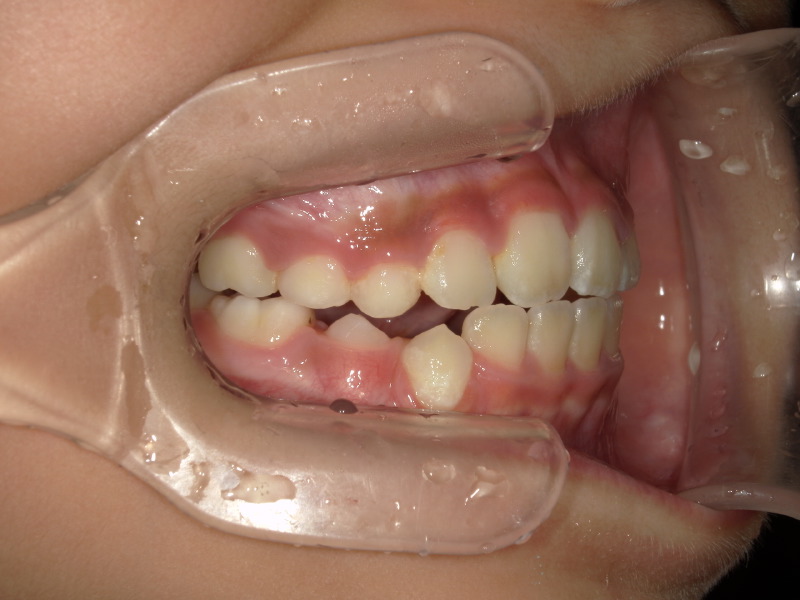

初めにこの女の子はそこまで歯並びは悪くないのかもしれません。

下の歯にがたつきはあるのですが今の生え変わりだけでは片方の前歯も出ていないためパッと見た時に歯並び、悪いかな?くらいになることも多いと思います。

切端咬合とは

乳歯の時の歯の写真を横から撮った画像です。

下は本来の乳歯の時の噛み合わせの横の写真です。

いつも噛み合わせは上の歯が少し前にありその少し後ろに下の歯が並びます。

上の顎が先に成長し、下の歯は後からグッと成長します。

このままの噛み合わせで成長をすると最終的に反対咬合になる可能性も出てきます。